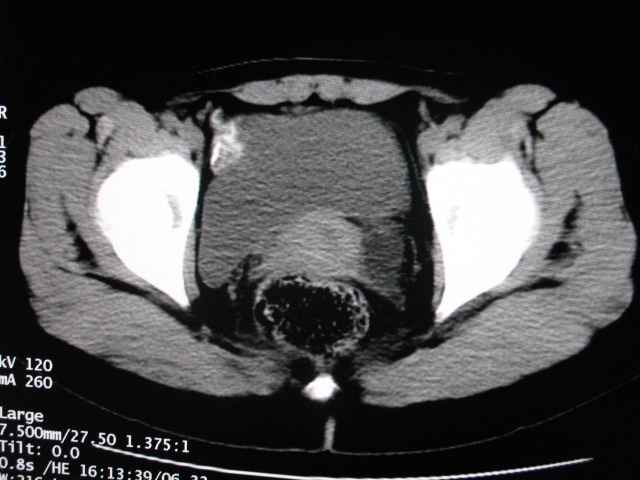

女,28岁,自觉腹部包块一年余

考虑左侧双肾盂双输尿管畸形,其中一输尿管末端梗阻(不排除异位开口可能)并相应之肾盂及输尿管明显扩张积水。

左双肾盂输尿管畸形.其一输尿管远端输尿管囊肿引起一肾盂输尿管积水.

考虑左侧双肾盂双输尿管畸形,其中一输尿管末端梗阻(不排除异位开口可能,不知病人有无不自觉溢尿,有可能开口于阴道或宫颈,也可下端为盲端)并相应之肾盂及输尿管明显扩张积水。

术后证实是左侧双肾盂双输尿管畸形,巨输尿管巨肾盂症